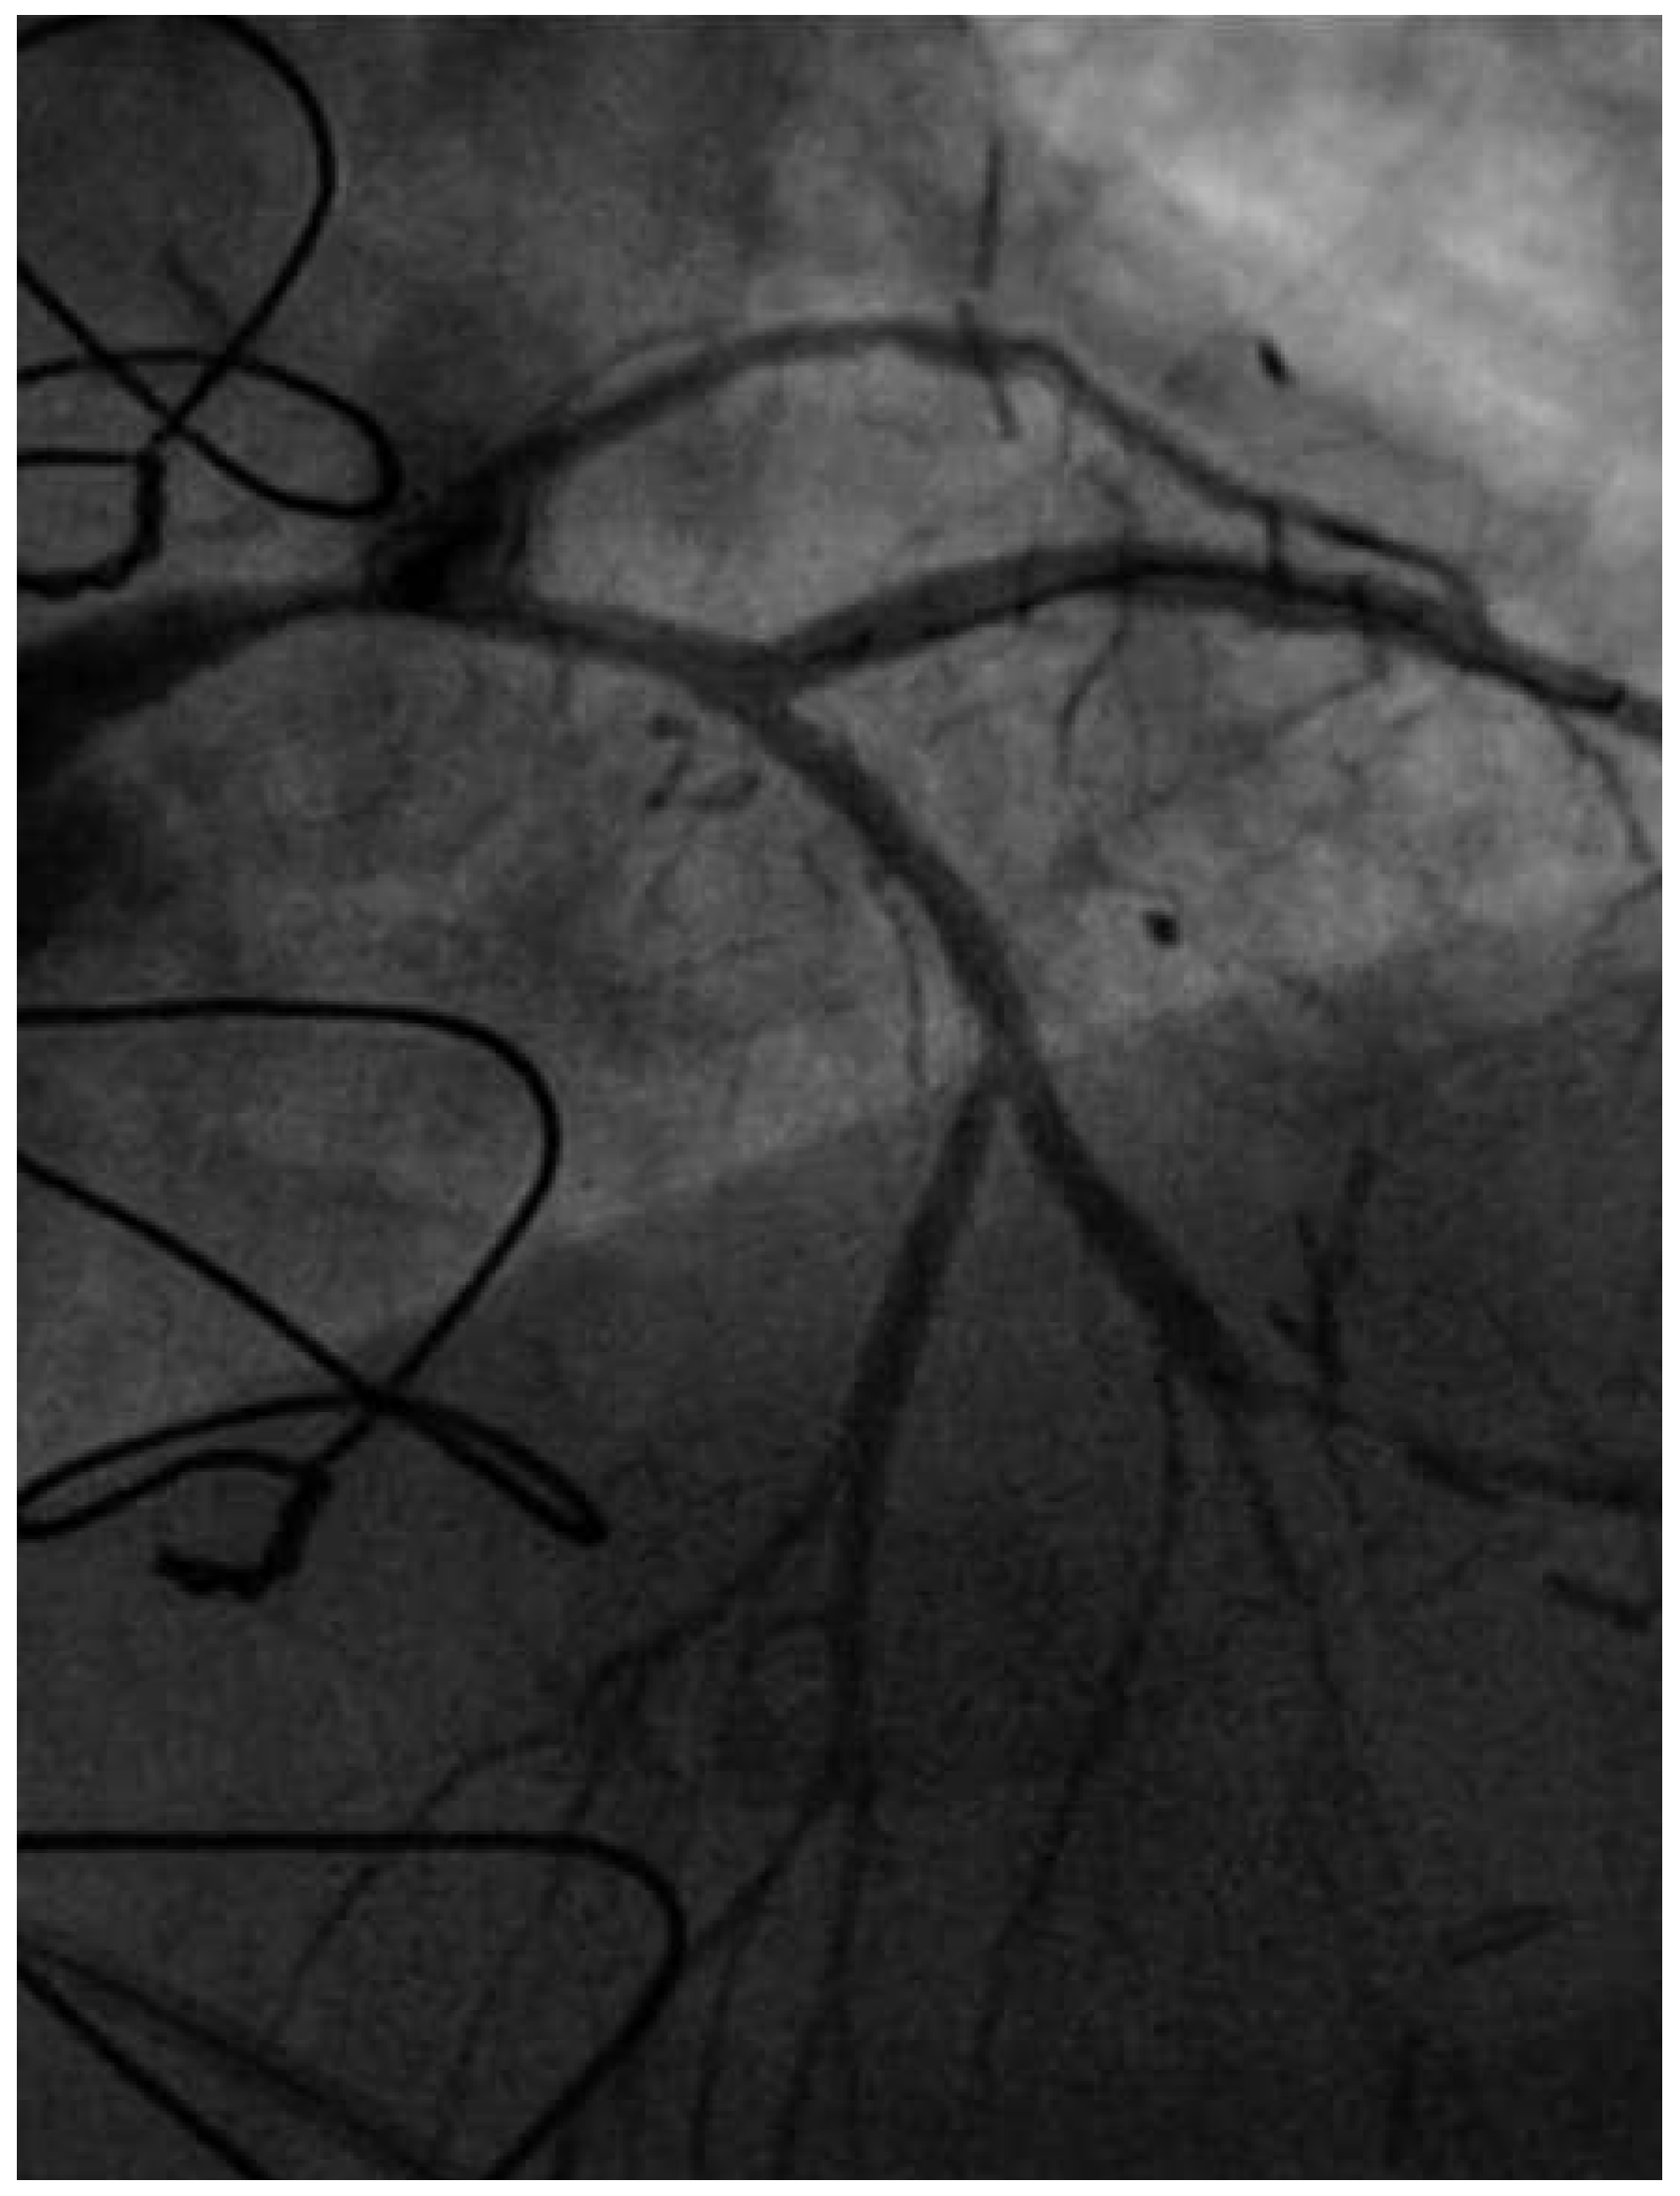

Coronary angiography of the left coronary system demonstrated severe left main stem (LMS) disease (Figure 1). The severe LAD in-stent restenosis was very eccentric and appeared to be restricting the origin of a sizeable diagonal branch, which also had severe disease. Distally, the LAD was occluded at the point where another stent had been inserted previously and just beyond a large septal perforator. The Cx had severe ostial disease and gave rise to a heavily diseased first obtuse marginal branch. The remainder of Cx and right coronary artery (RCA) systems were occluded proximally, with absent collaterals. The only patent graft was the LIMA, anastomosed very distally to the LAD (Figure 2). Following discussion, it was felt that neither Cx nor RCA were suitable targets for surgery and we therefore undertook intervention to the LMS and LAD / first diagonal bifurcation.

Figure 1. RAO 15°, cranial 40° view. of the left coronary system. Note the diseased LMS (A), the proximal LAD stent at the diagonal bifurcation (B) and the distal LAD stent (C).